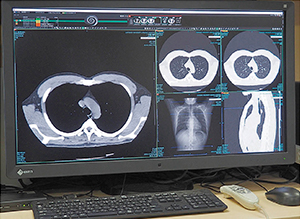

8メガのワイド液晶モニタ(右)とレポート表示用の21インチ縦型液晶モニタ(左)を組み合わせた読影端末 |

SYNAPSE SAI viewerのビューワ画面 |

読影用端末は,1階の放射線部門の読影室に9セットとマンモグラフィ用専用端末が1台,そのほか,CT室と医局,科長室にも設置されている。基本的な読影端末の構成は,画像表示用の8メガのワイド液晶モニタ1面と,レポートや電子カルテ表示用の21インチ縦型液晶モニタの組み合わせになっている。ワイド液晶モニタに2画面を分割して表示することで,2面構成よりもベゼル部分がなく広い視野が確保できる。京極教授は端末の構成について,「ワイドモニタの採用のほかPC本体を小さくして机上のスペースを広く取れるようにするなど,導入時には快適な読影環境になるように要望しました」と述べる。